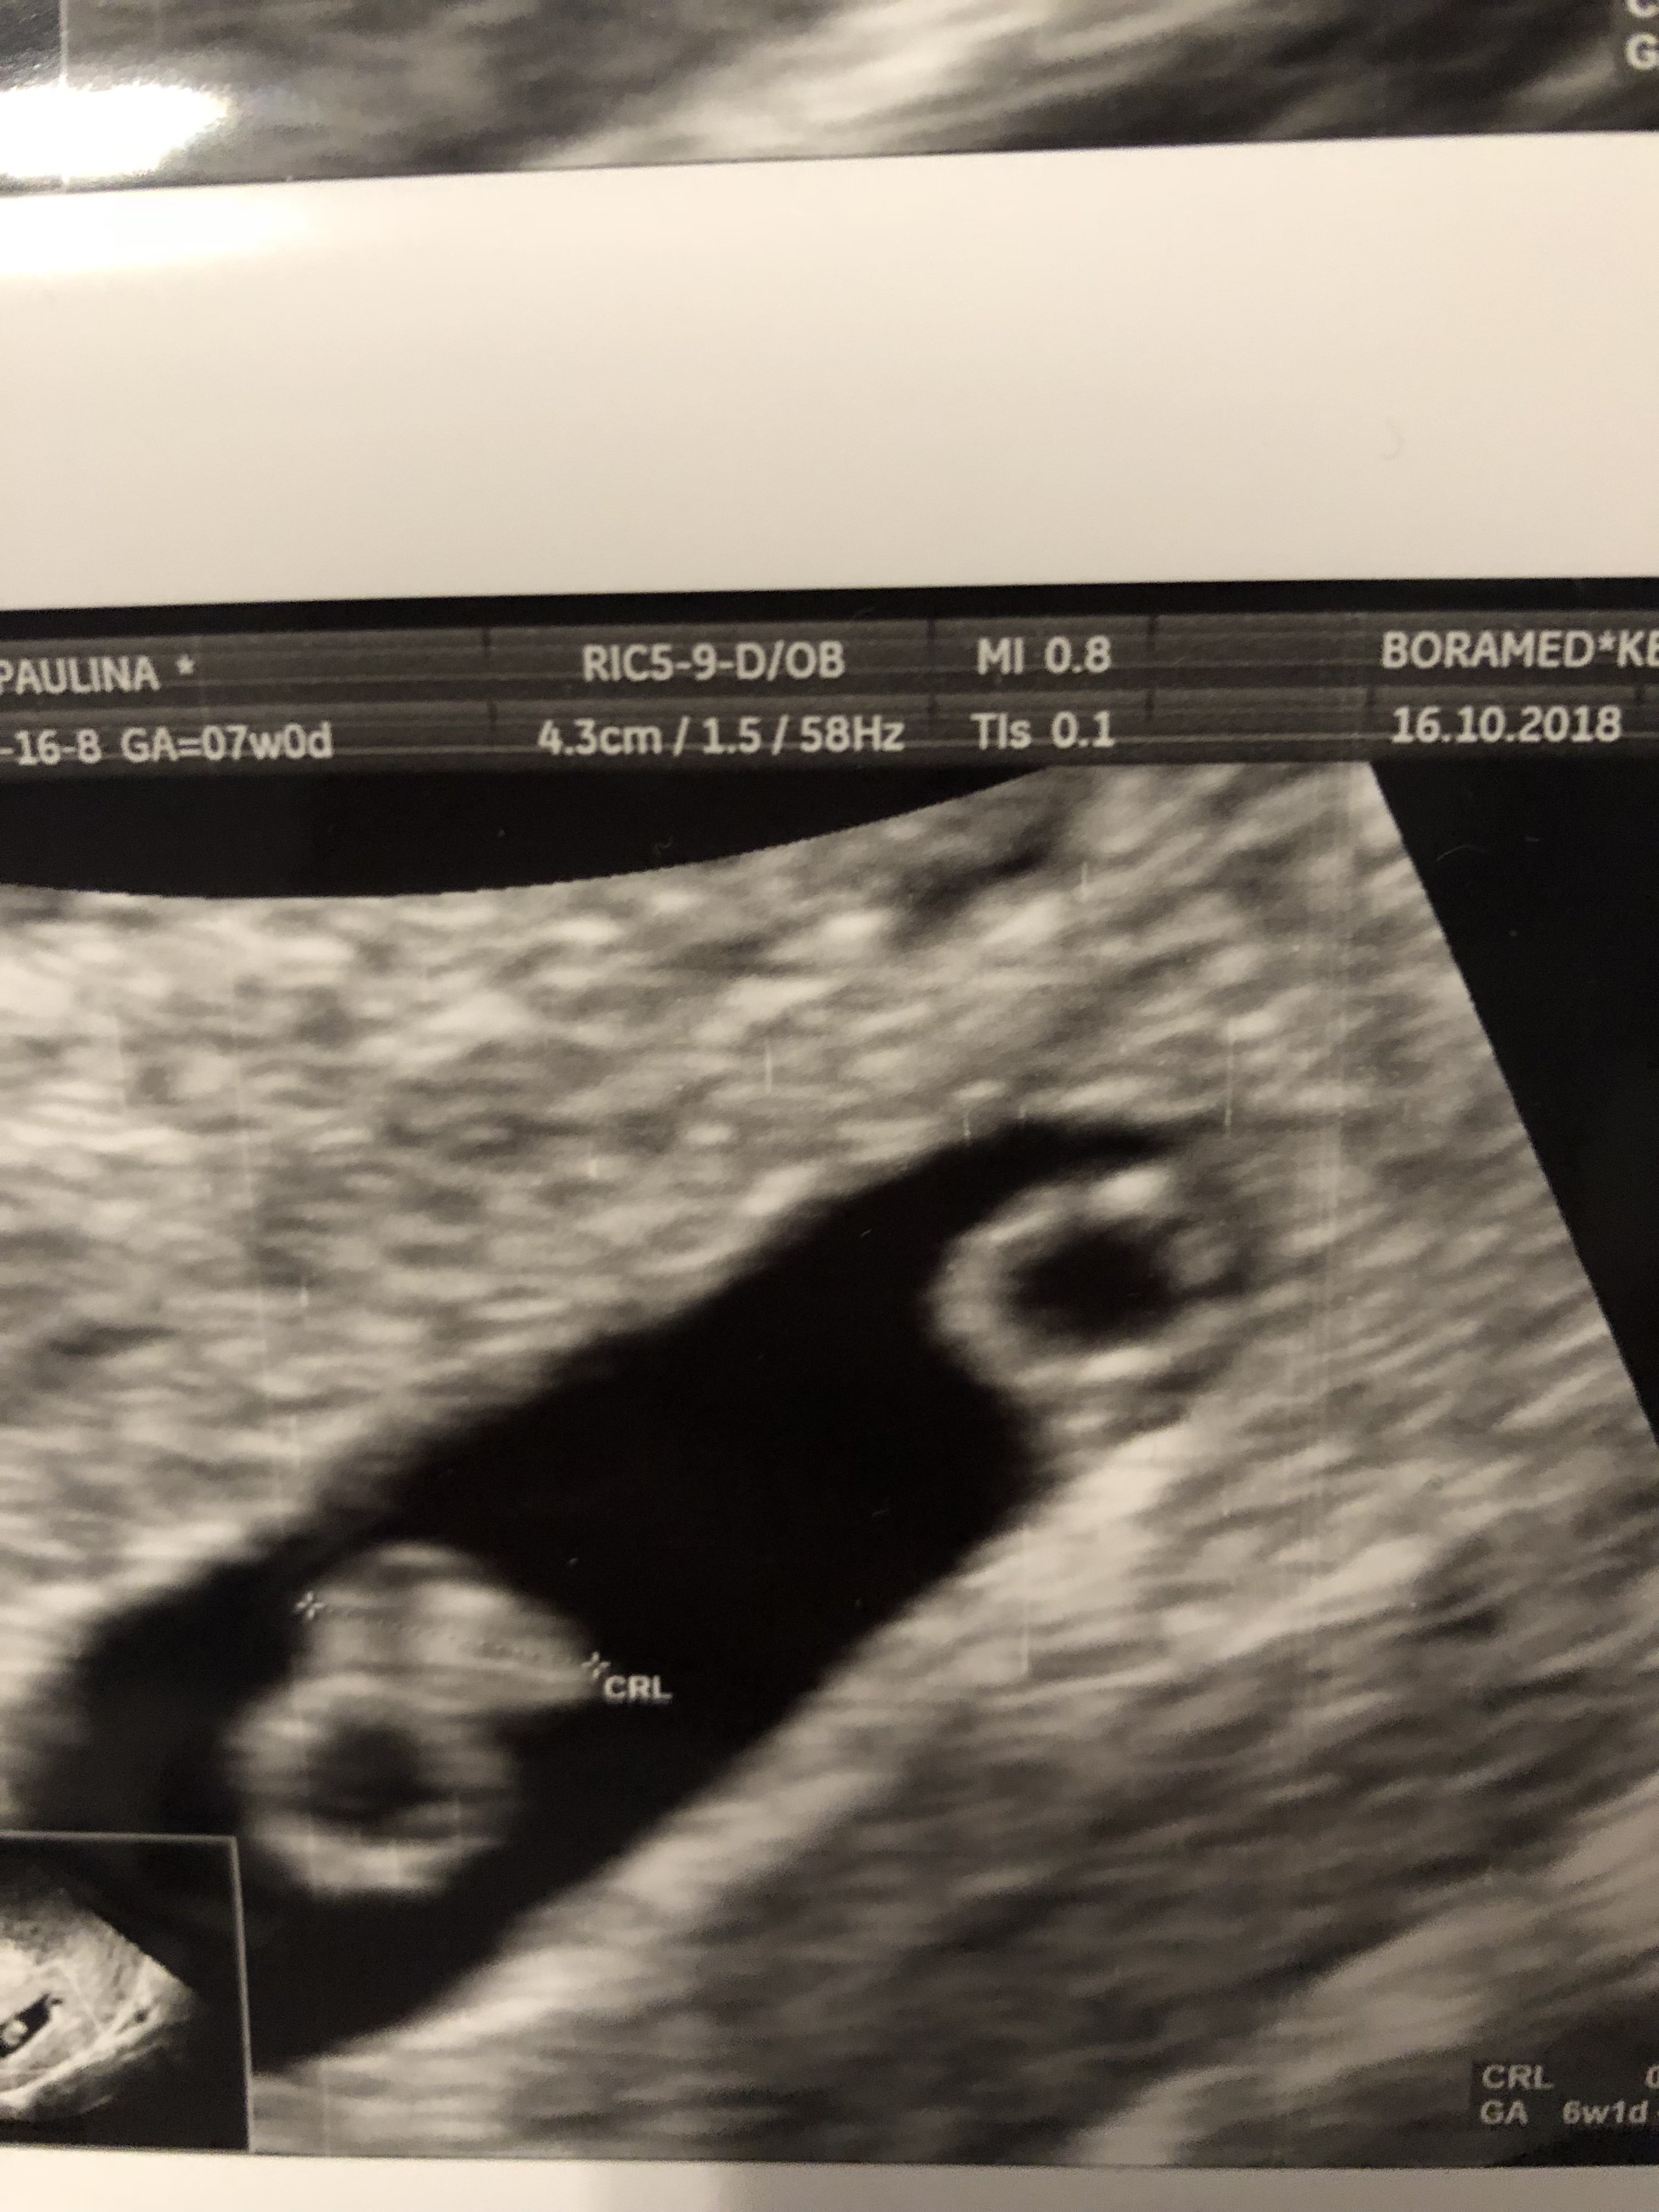

Wg teorii Ramziego to musi być 6-8 tydzień, później jest bardziej sprawdzająca się teoria, Nuba na podstawie wyrostków płciowych i usg z 12-14 tyg. Zobacz załącznik 908705

No oczywiścieto jest już 6 tydzień

, od 5+0 do 7+6 ponoć można sprawdzić